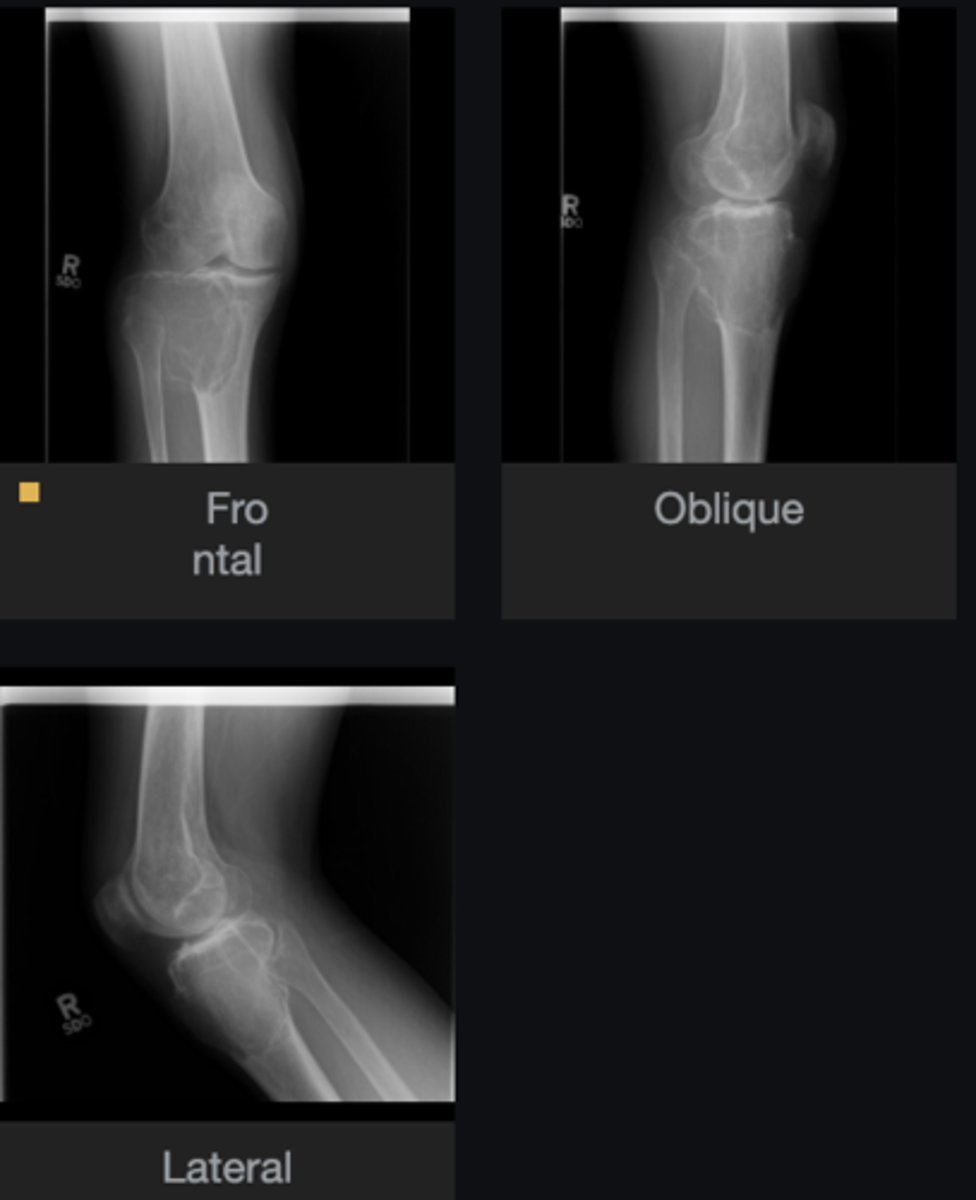

- Distal femur involved

- Elongated stalk

- Cortex and medulla are continuous

- Pointing away from joint

- Narrow base

Describe the bone lesion

<p>Describe the bone lesion</p>

Pedunculated solitary osteochondroma

Most likely diagnosis?

<p>Most likely diagnosis?</p>

Refer to orthopedist

Next step?

<p>Next step?</p>

- Fracture

- Malignant transformation (chondrosarcoma)

- Bursitis

- Neurologic injury

Concerns/complications?

<p>Concerns/complications?</p>